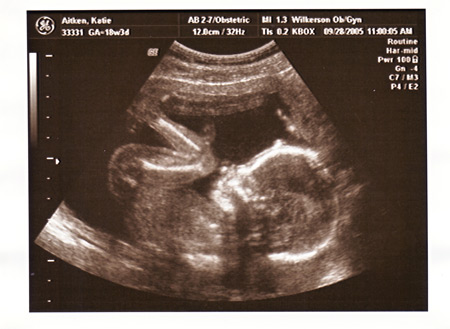

I had my ultrasound today, and found out everything is perfect and in place. We are so excited that Maeve will have a little sister to play with!!!